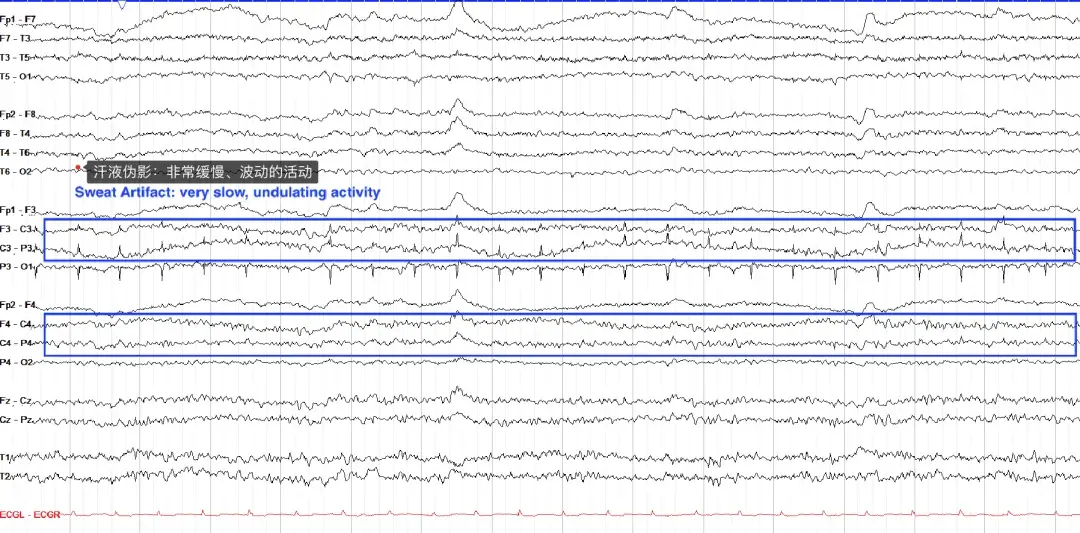

① 汗液伪影(Sweat artifacts)

汗液伪影的特点是非常缓慢(通常小于 0.5 Hz)、相对较低的振幅活动,这是因为汗液中的氯化钠携带电荷,被 EEG 电极拾取。汗液伪影在定位方面不必遵循特定模式,可以是双侧、单侧,甚至仅集中于几个电极。下面的示例在 P3 处也有电极伪影。